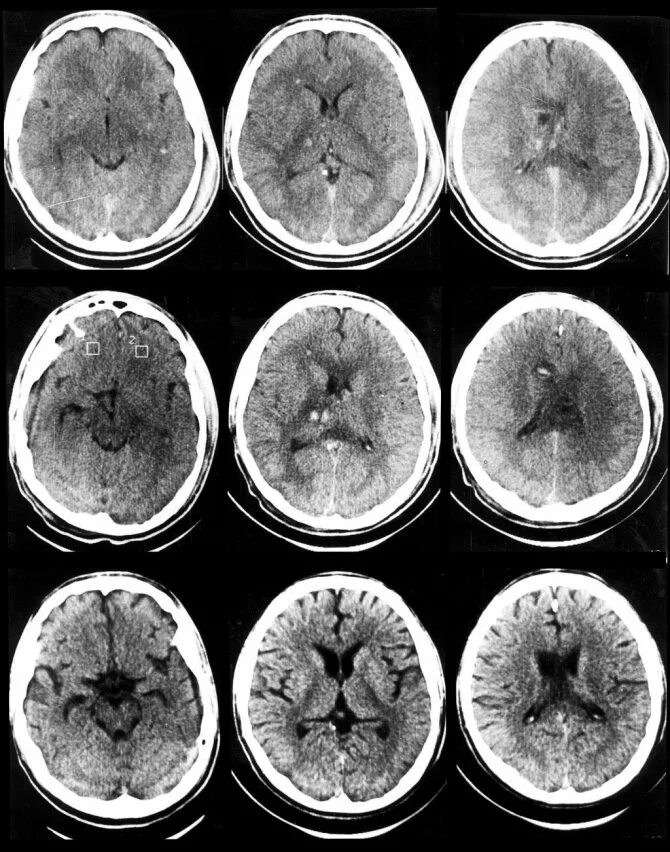

50 лет кт